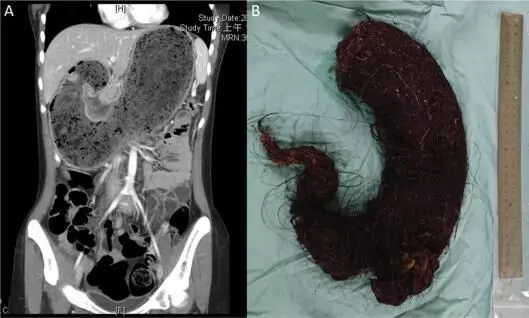

text_fieldsചണ്ഡിഗഡ്: കടുത്ത വയറുവേദനയും വിശപ്പില്ലായ്മയും കാരണം ആശുപത്രിയിലെത്തിയ അഞ്ചുവയസുകാരിയെ പരിശോധിച്ച ഡോക്ടർമാർ കണ്ടത് അമ്പരപ്പിക്കുന്ന കാഴ്ച്ച. സ്കാനിങ്ങിനിടെ കുട്ടിയുടെ വയറിനുള്ളിൽ മുടിയുടെ വലിയ ശേഖരം കണ്ടെത്തുകയായിരുന്നു. തുടർന്ന് നടത്തിയ ശസ്ത്രക്രിയയിൽ ഒന്നര കിലോ വരുന്ന മുടിയുടെ വലിയ ഉരുള ഡോക്ടർമാർ നീക്കം ചെയ്തു. ചണ്ഡിഗഡിലെ മൗലി ജാഗ്രാനിലാന് സംഭവം.

പഞ്ചകുളയിലെ സിവിൽ ഹോസ്പിറ്റലിൽ ഡോ. വിവേക് ഭാദുവിെൻറ നേതൃത്വത്തിലുള്ള സംഘമാണ് ശസ്ത്രക്രിയ നടത്തിയത്. കുട്ടിയെ സൂക്ഷ്മമായി നിരീക്ഷിക്കാനും സ്വന്തം മുടി മുറിച്ചുമാറ്റാനും മാതാപിതാക്കളോട് നിർദ്ദേശിച്ചിട്ടുണ്ടെന്നും ഡോക്ടർ പറഞ്ഞു. കുട്ടി ഇപ്പോഴും നിരീക്ഷണത്തിലാണ്.'ട്രൈക്കോബെസോർ'എന്ന് വിളിക്കുന്ന അവസ്ഥയാണ് കുട്ടിയിൽ കണ്ടതെന്ന് ഡോക്ടർ വിവേക് പറഞ്ഞു. ദഹനനാളത്തിനുള്ളിൽ മുടി അടിഞ്ഞുകൂടുന്നതുകാരണം ആമാശയത്തിന് വീക്കം, വേദന, വിശപ്പ് കുറയൽ എന്നിവ ഉണ്ടാവും. വയറുവേദന കാരണം പെൺകുട്ടിയുടെ മാതാപിതാക്കൾ ഒരാഴ്ചമുമ്പ് തന്നെ സന്ദർശിക്കുകയായിരുന്നുവെന്നും അദ്ദേഹം കൂട്ടിച്ചേർത്തു.

രണ്ടര വർഷമായി കുട്ടി മുടി കഴിക്കുകയായിരുന്നുവെന്നാണ് ഡോക്ടർമാരുടെ നിഗമനം. 'ഈ അവസ്ഥ പ്രധാനമായും മാനസിക വിഭ്രാന്തി ബാധിച്ചവരിലോ കടുത്ത സമ്മർദ്ദം നേരിടുന്നവരിലോ ആണ് കാണുന്നത്. കുട്ടികൾക്കിടയിൽ ഇത് വളരെ അപൂർവമാണ്. ഞാൻ 20 വർഷമായി ഇവിടെ ജോലിചെയ്യുന്നു. കുട്ടികൾക്കിടയിൽ ഇത്തരത്തിലുള്ള സംഭവം കാണുന്നത് ആദ്യമാണ്'-ഡോ. വിവേക് പറഞ്ഞു.

'മുടി ദഹിക്കാത്തതിനാൽ ദഹനവ്യവസ്ഥയിൽ ഇവ തങ്ങിനിൽക്കും. ഒരാൾ മുടി കഴിക്കുന്നത് തുടരുകയാണെങ്കിൽ, അത് ഒരു പന്ത്പോലെ ആകും. പോഷകാഹാരക്കുറവ്, വയർ വീക്കം, വേദന എന്നിവയിലേക്ക് ഇത് നയിക്കും'-അദ്ദേഹം പറഞ്ഞു.